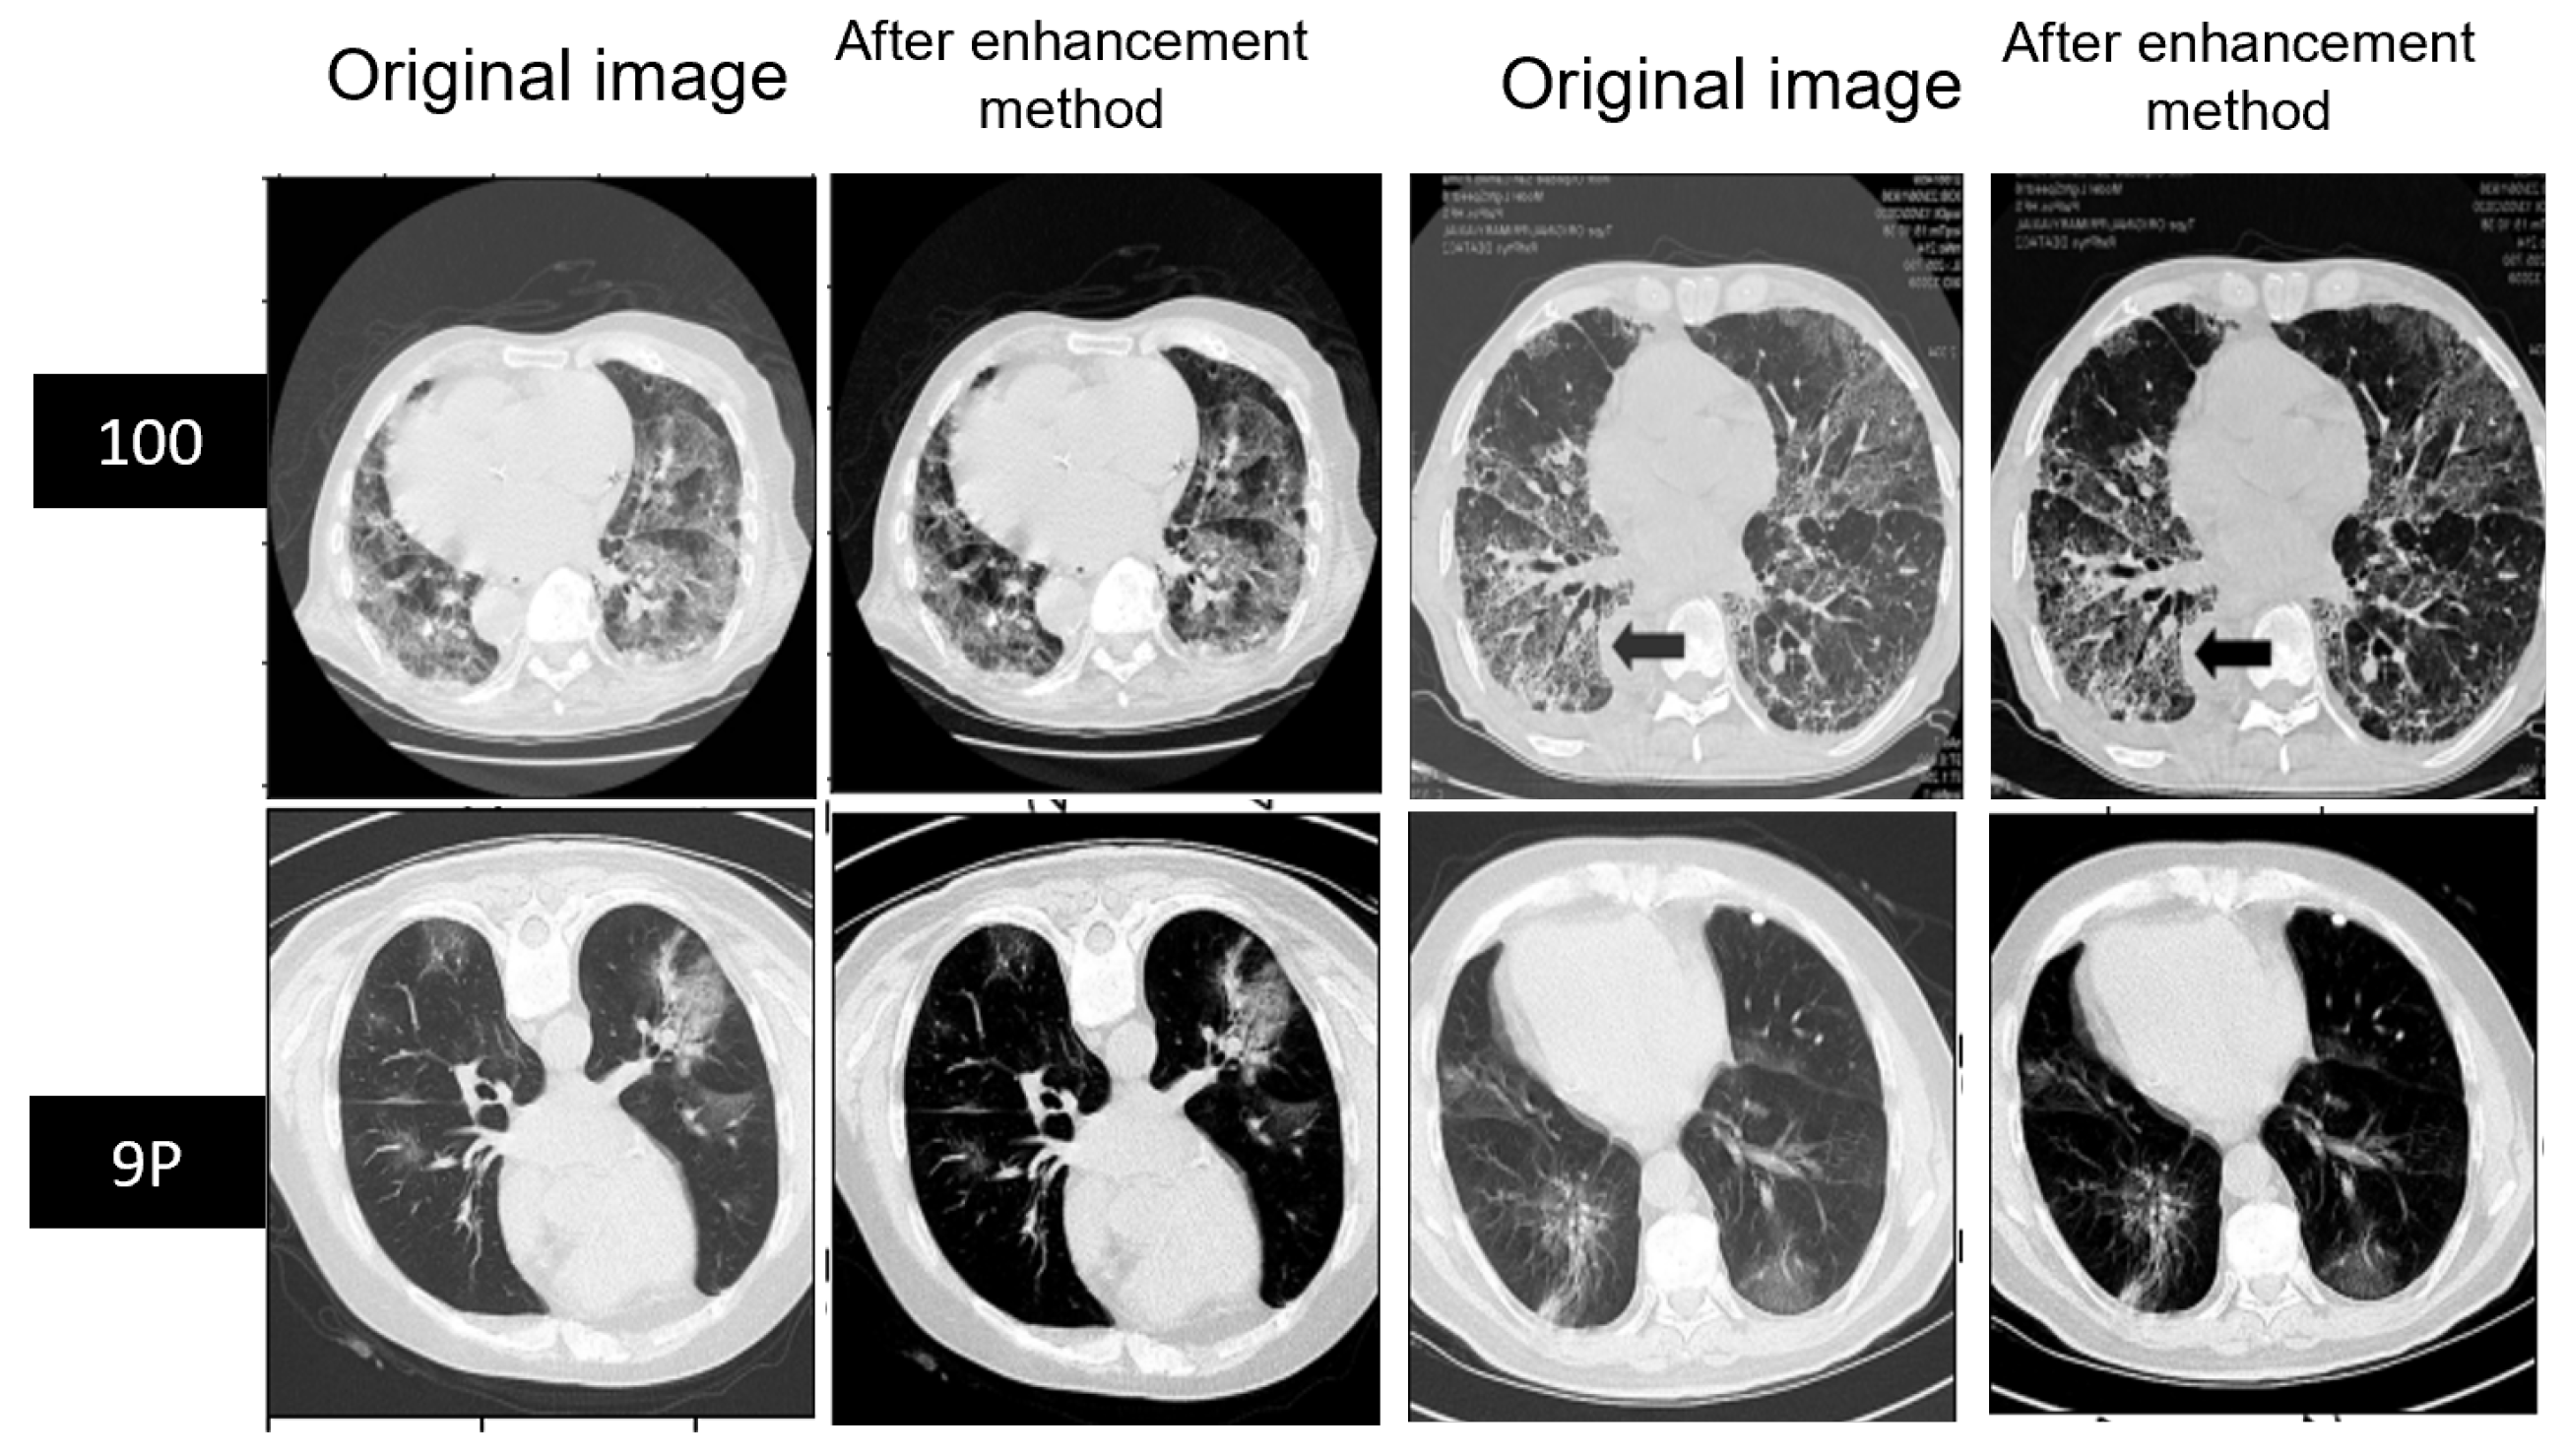

5.1. Preprocessing of MedSeg and Radiopaedia 9P Datasets

5.2. Preprocessing of Zenodo 20P Dataset